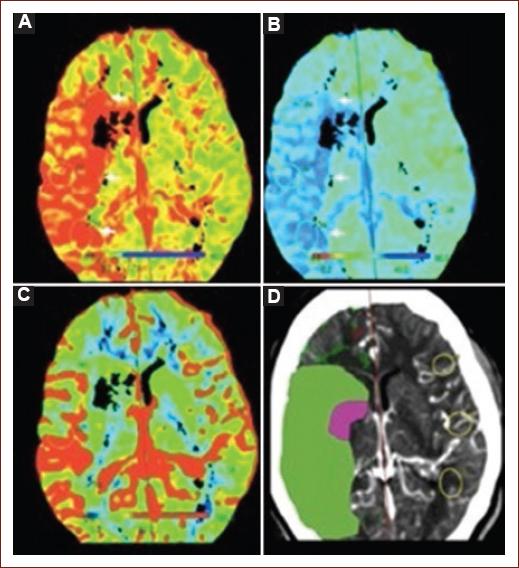

Computed tomography (CT) perfusion

Perfusion imaging, using either CT or MRI, has been used to select patients for treatment outside the recommended time window. Perfusion studies use contrast to measure the amount and time it takes for intravenous contrast to pass through certain areas of the brain and can help identify the ischemic core and penumbra. Recent studies (DAWN37 and DEFUSE 338) showed improved outcomes after MT for patients selected by specific parameters or perfusion. Its primary role in AIS is determining whether brain tissue is hypoperfused and, therefore, at risk of infarction. Penumbra (viable tissue) is the target for reperfusion therapy. CTP can be performed in a few minutes and gives us a number of measures, especially CBF and CBV. During acquisition for a CTP, the brain is repeatedly scanned during the passing of intravenous contrast throughout the brain parenchyma. As the contrast flows, the relative increase, peak, and the decrease in radiodensity create an attenuation-time curve. These curves are calculated for an arterial and venous input function and outflow, allowing to measure perfusion for each voxel. Unlike multiphase CTA, CTP involves acquiring many such images, which results in a higher radiation dose than CTA. This repeated scanning of the brain allows the generation of estimates for CBF, blood volume, median transit time, time to peak (TTP), time to drain, and tissue permeability. These measurements are shown in color-coded parametric maps, representing each variable. The ischemic core is identified by markedly reduced CBF and reduced CBV, with a marked delay in TTP and mean transit time. By contrast, the ischemic penumbra, which usually surrounds the ischemic core, has prolonged mean transit time but has only moderately reduced CBF and near-normal or even increased CBV (Fig. 4)17. It is now established that its use does not delay rtPA application, nor intervention through MT when compared to NCCT39, and it is associated with more reperfusion therapy use40. A systematic review of AIS diagnosis with CTP showed high sensitivity (80-82%) and very high specificity (95%). Its limitation in AIS includes that it can miss lacunar infarcts and has a relatively low sensitivity for posterior circulation infarcts41. CTP may also cause significant delays in workflow due to the longer acquisition and processing times and does not invariably provide accurate information. Several studies have shown that automated processing of CTP can provide a quantitative mismatch classification. Recently, DAWN37 and DEFUSE 338 used automated software (RAPID) to determine the ischemic core and showed excellent clinical outcomes in patients treated up to 24 h from symptom onset.

Figure 4 CTP with mismatch due to a large region of ischemic penumbra (salvageable hypoperfused tissue), compared to the ischemic core (unsalvageable tissue). A: CBF map shows a region of decreased perfusion within the right MCA territory (white arrowheads). B: median transit time map shows an increased blood contrast time that matches the same region as (white arrowheads). C: CBV map demonstrates no abnormality. D: large ischemic penumbra (green) with a small ischemic core (purple), representing a CTP mismatch. CBF: cerebral blood flow; CBV: cerebral blood volume; CTP: computed tomography perfusion; MCA: middle cerebral artery; MTT: median transit time.